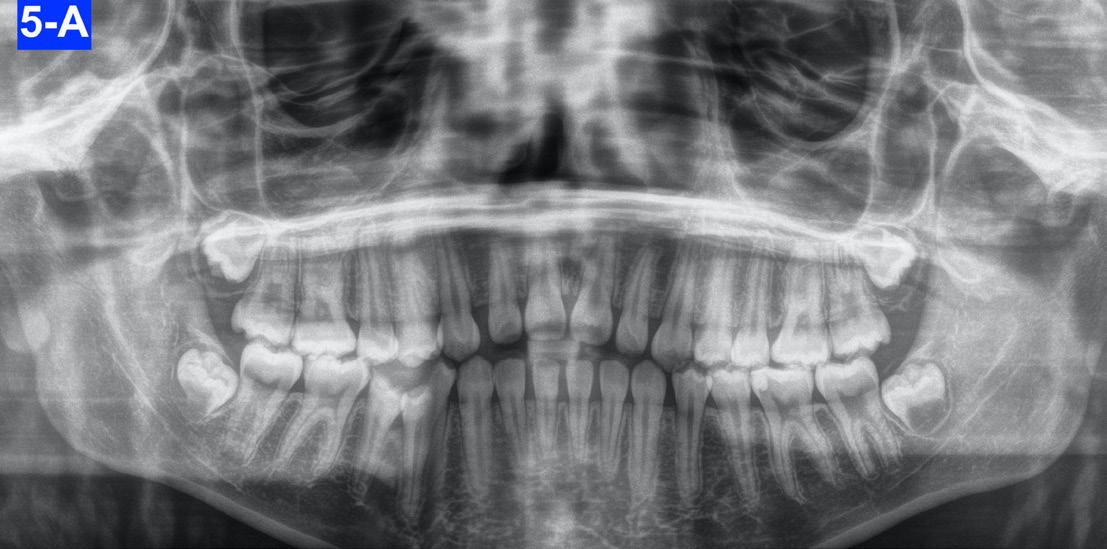

Panoramic radiogram revealed a complete permanent dentition with four impacted wisdom teeth. There was excellent bone support and no signs of periodontal or periapical pathology (Figure 5-A).

A healthy 12-year-7-month-old female, with an adult dentition, presented with a chief complaint of “teeth not coming in straight,” as was identified to her and her parents by a referring dentist. On clinical examination, the patient had pleasing facial esthetics on an orthognathic skeletal base. Intraorally, the patient had Angle Class I molar relationship bilaterally with well-aligned arches but impacted mandibular second molars with partially visible crowns (Figure 1). The panoramic radiograph confirmed the mesioangular impactions of the mandibular second molars bilaterally along with the third molars at the early crown calcification stage of development (Figure 1). An increase in inclination of second molars can be seen bilaterally, on examination of panoramic radiographs at ages of 10 years and 5 months and 11 years 10 months, which were 17 months apart (Figures 1 and 2).

Fig. 1: Initial presentation of mesioangular impacted mandibular second molars at 10 years and 5 months of age. Note that the mandibular third molars are at about a third crown completion stage of development.only for the understanding purpose.

Fig. 2: Follow-up radiograph at the age of 11 years and 10 months, 17 months after the initial detection of the mandibular second molar impactions. Note that the mesioangular inclinations of both molars had worsened with the further crown development of the mandibular third molar crowns and their positions translating superiorly.